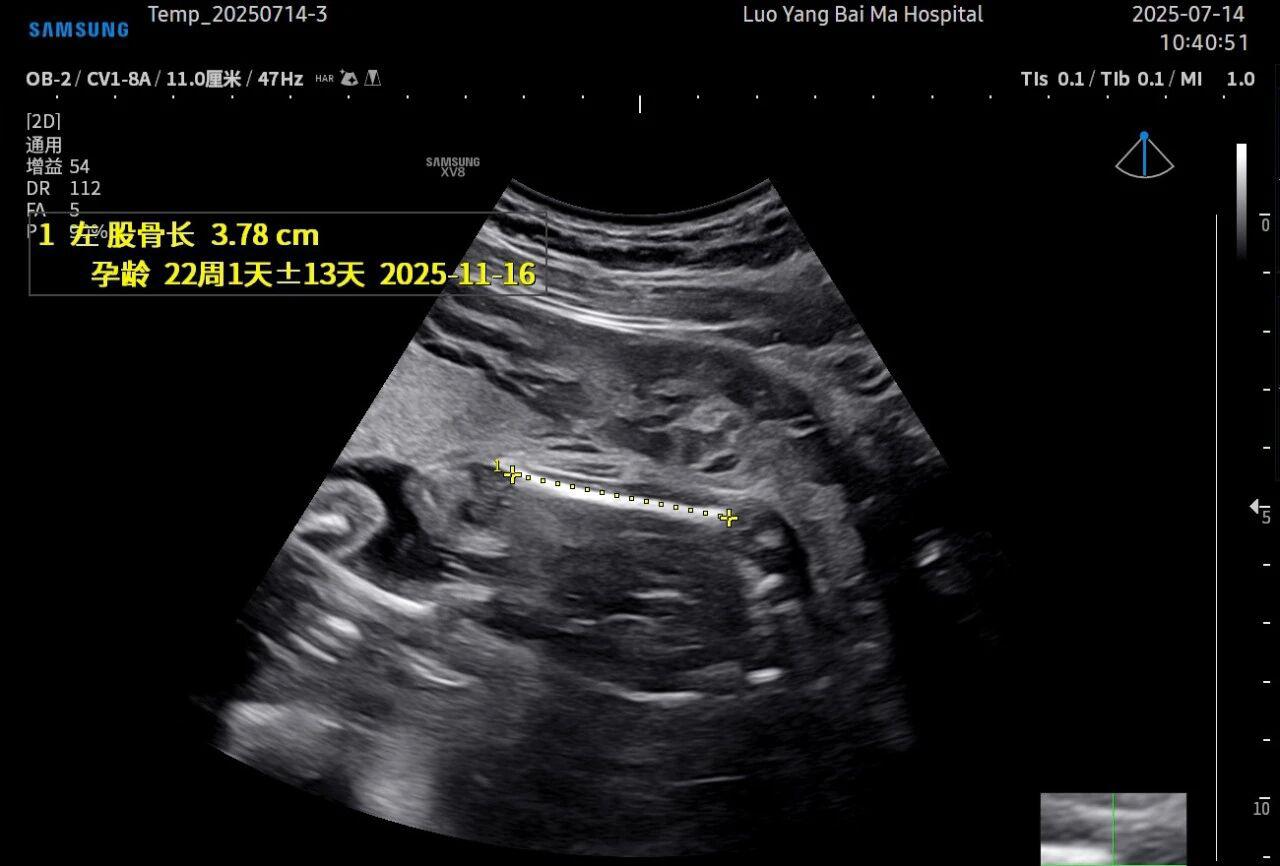

孕中期(通常在22-28周)的大排畸检查是整个孕期至关重要的环节之一。其目的在于系统地筛查胎儿是否存在结构性异常,如唇裂、脊柱裂、大脑、心脏、骨骼发育不良等问题。在这一关键检查中,5D智能彩超凭借其技术特性,展现出了显著的优势。

这是5D技术的核心优势之一。系统内置了强大的智能化大数据分析功能和AI辅助诊断工具。例如,在进行胎儿颈项透明层(NT)测量、胎儿长骨(LB)测量等关键生物学指标评估时,5D智能系统可以自动识别解剖层面、智能勾勒测量范围并进行计算。这不仅大大缩短了检查时间,更重要的是,它通过标准化的智能算法减少了因人为操作可能产生的误差,使诊断结果更加客观、可靠。